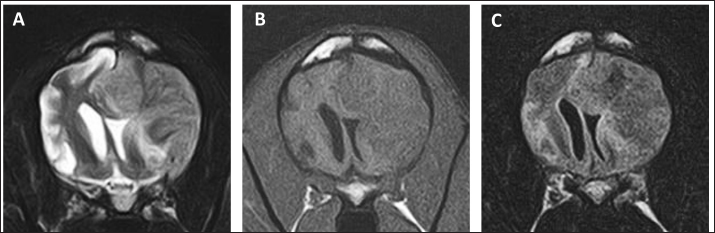

On day 99, the patient presented with acute onset of somnolence and recumbency. Cerebral infarction was suspected because the entire right cerebral hemisphere and part of the thalamus showed high signal intensity on T2WI and FLAIR images, high signal intensity on diffusion weighted Imaging (DWI) images, and equal signal intensity on the ADC map (Fig. 4). MRI at this time demonstrated that the HS lesion in the left frontal lobe was 28.1 × 24.3 × 22.2 cm in size and had clearly regressed (Fig. 1G–I). The patient was also prescribed rivaroxaban (0.25 mg/kg, twice a day; Xarelto tablets 10 mg; Bayer Yakuhin, Osaka, Japan), and the owners were instructed to perform follow-up at home. The patient's neurological symptoms gradually improved, and a third dose of ACNU was administered at 20 mg/m2 on day 110. However, on day 124, an MRI was performed because a neurological examination revealed a decrease or loss of facial sensation, and trigeminal nerve injury was suspected. Although a contrast agent could not be used because the procedure was performed without anesthesia, clear re-enlargement of the HS lesions was observed (Fig. 5). ACNU was therefore changed to temozolomide (Temozolomide Tablets 20 mg “NK,” Nippon Kayaku, Tokyo, Japan), which was administered at an oral dose of 120-140 mg/m2 once daily for 5 days over a 28-day cycle on day 131, 153, and 173. During this time, there were no major changes in the patient's clinical symptoms, and the patient was able to walk with some unsteadiness. However, the patient died suddenly on day 195. A pathological autopsy was not performed at the owner's request.

Fig. 5. MR images of the case on day 124. Re-enlargement of the lesion was observed on (A) T2-weighted, (B) T1-weighted, and (C) FLAIR images.